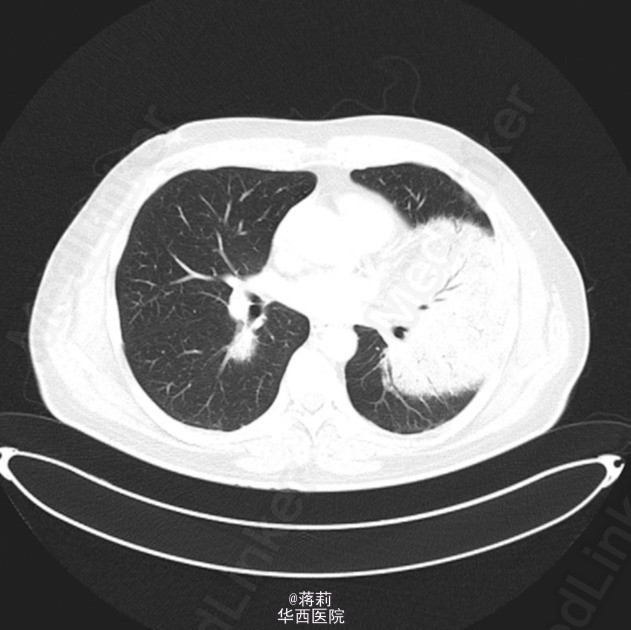

稀罕病例,大家一起来学习下!粘膜相关淋巴组织(MALT)淋巴瘤多见于胃部,而原发性肺 MALT 淋巴瘤十分罕见。来自南非开普敦 Sellenbosch 大学和 Tygerberg 医院呼吸科、血液科、病理科的数名学者近期在 Chest 杂志上报道了这样一例患者。 MALT 淋巴瘤有着较好的转归,5 年生存率达到 85% 以上,一般生存时间可超过 10 年。不像其他大多数肿瘤,即使在诊断时已有转移,也不会影响其预后或生存率。详见:http://journal.publications.chestnet.org/article.aspx?articleID=1900893